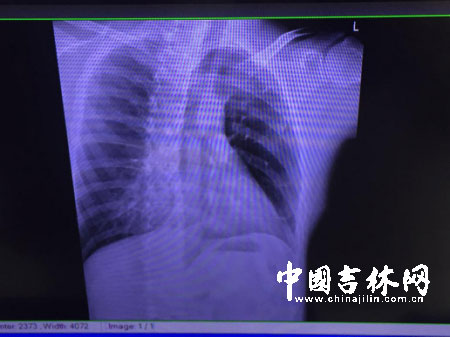

“当时晕了好一会儿吧,感觉自己已经动不了了。”被紧急送医的沈杭在当地医院做了CT检查,医生拿着报告单说,“百分之九十是骨折,也可能是骨裂,19号最好来复诊,建议你们不要坐飞机。”

10日上午,长春中日联医院的360°CT结果显示,沈杭的第8根肋骨骨折,第9根肋骨骨裂。他不得不暂停工作,留在家中休养。

沈杭在泰所拍摄的CT检查结果